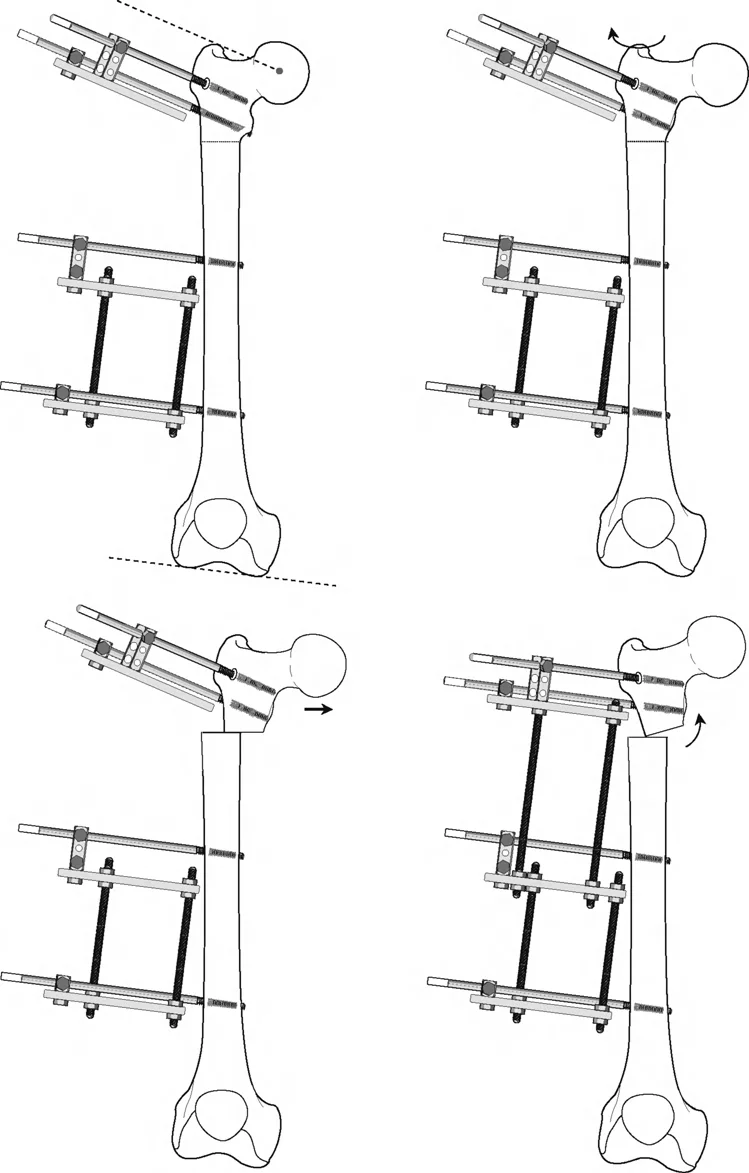

المفصلات القريبة من المفصل وقواعد قطع العظم (Osteotomy Rules)

عند التعامل مع التشوهات الواقعة بالقرب من خط المفصل - مثل التقوس الشديد في الجزء العلوي من الساق (مرض بلونت) أو التشوه الفحجي في الجزء السفلي من عظم الفخذ - يصبح وضع الجهاز مقيدًا هندسيًا. إن المتطلبات البيولوجية للحفاظ على كبسولة المفصل، وتجنب وضع الأسلاك داخل المفصل، ومنع التهاب المفاصل القيحي، غالبًا ما تجبر الجراح على وضع الحلقة المرجعية على مستوى مختلف تمامًا عن مركز دوران الانحراف (CORA) الفعلي.

تحدي مركز دوران الانحراف (CORA) القريب من المفصل

لمطابقة مفصلة المثبت الخارجي مع المستوى الدقيق لمركز دوران الانحراف (CORA)، يجب غالبًا بناء المفصلة فوق أو تحت مستوى الحلقة الفعلية. يُعرف هذا في مبادئ بالي باسم تجميع المفصلة القريبة من المفصل (juxta-articular hinge assembly).

إذا كان مركز دوران الانحراف (CORA) يقع بالقرب من خط المفصل، فإن وضع حلقة إليزاروف القياسية عند هذا المستوى بالضبط مستحيل دون انتهاك مساحة المفصل أو شد الهياكل الكبسولية الحيوية. لذلك، يتم تثبيت الحلقة المرجعية بالعظم الكثيف أو العظم الطويل المتاح، ويتم بناء آلية المفصلة باستخدام قضبان ملولبة، ولوحات توصيل، ودعامات. ثم يتم "إنزالها" (أو رفعها) لتتطابق تمامًا مع مركز دوران الانحراف (CORA) الهندسي الحقيقي.

في المنشآت القريبة من المفصل، غالبًا ما نعتمد على قاعدة قطع العظم 2. نظرًا لأنه لا يمكننا قطع العظم بأمان عند خط المفصل تمامًا (مركز دوران الانحراف CORA)، فإننا نقطع العظم في مستوى أدنى في منطقة الميتافيسيس. بعد تحقيق التصحيح الزاوي عبر المفصلات (محور تصحيح الانحراف ACA)، يتم إعادة محاذاة خطوط المحور الميكانيكي بشكل مثالي، ولكن نهايات العظم في موقع قطع العظم تتحرك بالنسبة لبعضها البعض.

قيود الأسلاك والدبابيس في القاعدة 2

لتحقيق هذه الترجمة الضرورية والمقصودة بسلاسة باستخدام إطار دائري كامل الأسلاك، يلزم استخدام أسلاك الزيتون المعاكسة (counter-opposed olive wires). تعمل أسلاك الزيتون كقوى سحب ديناميكية، تسحب قطعة العظم على طول الحلقة أثناء فتح المفصلات. بدون أسلاك الزيتون، سيبقى العظم ثابتًا بينما تتحرك الحلقة عبر الأنسجة الرخوة، مما يسبب نخرًا شديدًا في الجلد.

على العكس من ذلك، إذا تم استخدام دبابيس نصفية (مسامير شانز)، فإنها تقيد العظم بطبيعتها بالحلقة. نظرًا لأن الدبابيس النصفية هي أذرع صلبة (مثبتة من طرف واحد بالحلقة ومغروسة في العظم من الطرف الآخر)، فإنها لا تسمح للعظم بالانزلاق على طول محور السلك. هذا يجعل أسلاك الزيتون غير ضرورية للترجمة في منشآت الدبابيس النصفية، ولكنه يتطلب من الجراح التأكد من أن الدبابيس النصفية قوية بما يكفي (عادةً دبابيس بقطر 5 مم أو 6 مم مطلية بهيدروكسي أباتيت) لتحمل لحظات الانحناء الناتجة عن الترجمة.

نصائح جراحية للمنشآت القريبة من المفصل

| المبدأ | التطبيق السريري | تحذير / خطأ محتمل |

|---|---|---|

| التحقق من CORA | دائمًا تحقق من CORA الحقيقي في الأشعة السينية الطويلة للطرفين قبل بناء المفصلة. | الاعتماد على الأشعة السينية القصيرة للركبة سيؤدي إلى CORA غير دقيق وبالتالي سوء محاذاة. |

| ACA العمودي | تأكد من أن محور المفصلة (ACA) عمودي تمامًا على مستوى التشوه. | محور ACA مائل سيحدث تشوهًا ثانويًا غير مرغوب فيه (مثل تصحيح التقوس ولكن إحداث الانحناء الأمامي). |

| تخليص الأنسجة الرخوة | عند استخدام قاعدة قطع العظم 2، احسب الترجمة المتوقعة وتأكد من أن الأنسجة الرخوة يمكن أن تستوعبها. | عدم مراعاة الترجمة يمكن أن يتسبب في اصطدام العظم بالجلد، مما يؤدي إلى النخر. |

| تقابل الأسلاك | استخدم ما لا يقل عن سلكين زيتون متقابلين لكل قطعة إذا كنت تتجنب الدبابيس النصفية. | الأسلاك الزيتون الفردية ستسبب قصًا ودورانًا غير مرغوب فيه حول محور السلك. |